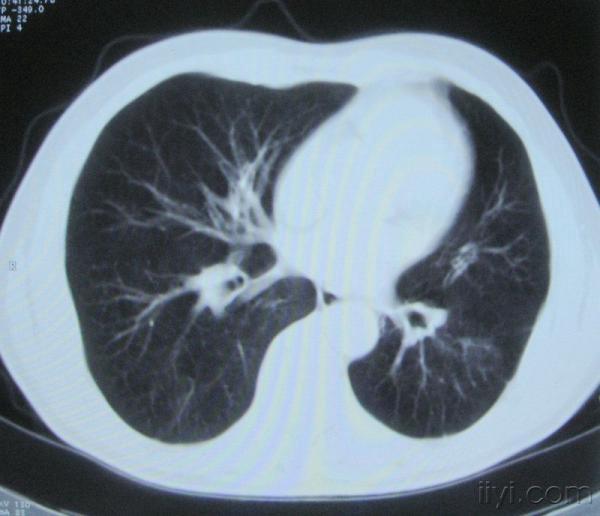

男。60岁,胸片示支气管炎治疗后复查CT。

你指那个肯定是淋巴结,中央系坏死,这很常见,特别在双侧腹股沟会经常看到。这个双侧腋窝及纵隔见多发小淋巴结征。

根据位置考虑应该是淋巴结,密度不均,是因为肿大的淋巴结中心液化坏死